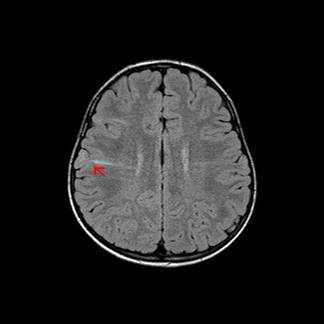

为了查明病因并进一步治疗,家人带小月来到广东三九脑科医院,入院后完善了相关检查,头部MR提示:右侧脑室体后部室管膜下示一结节状稍低信号影,无明显占位效应;双侧大脑半球皮层及皮层下示多发斑片状高信号影,结节性硬化。脑电图报告显示:双侧颞、中央区及右侧顶区可见少量中高波幅棘-慢波非同步发放,以右侧最为明显。脑磁图提示:发作间期,发作期癫痫灶位于右侧中央区可能性大。

术前MR